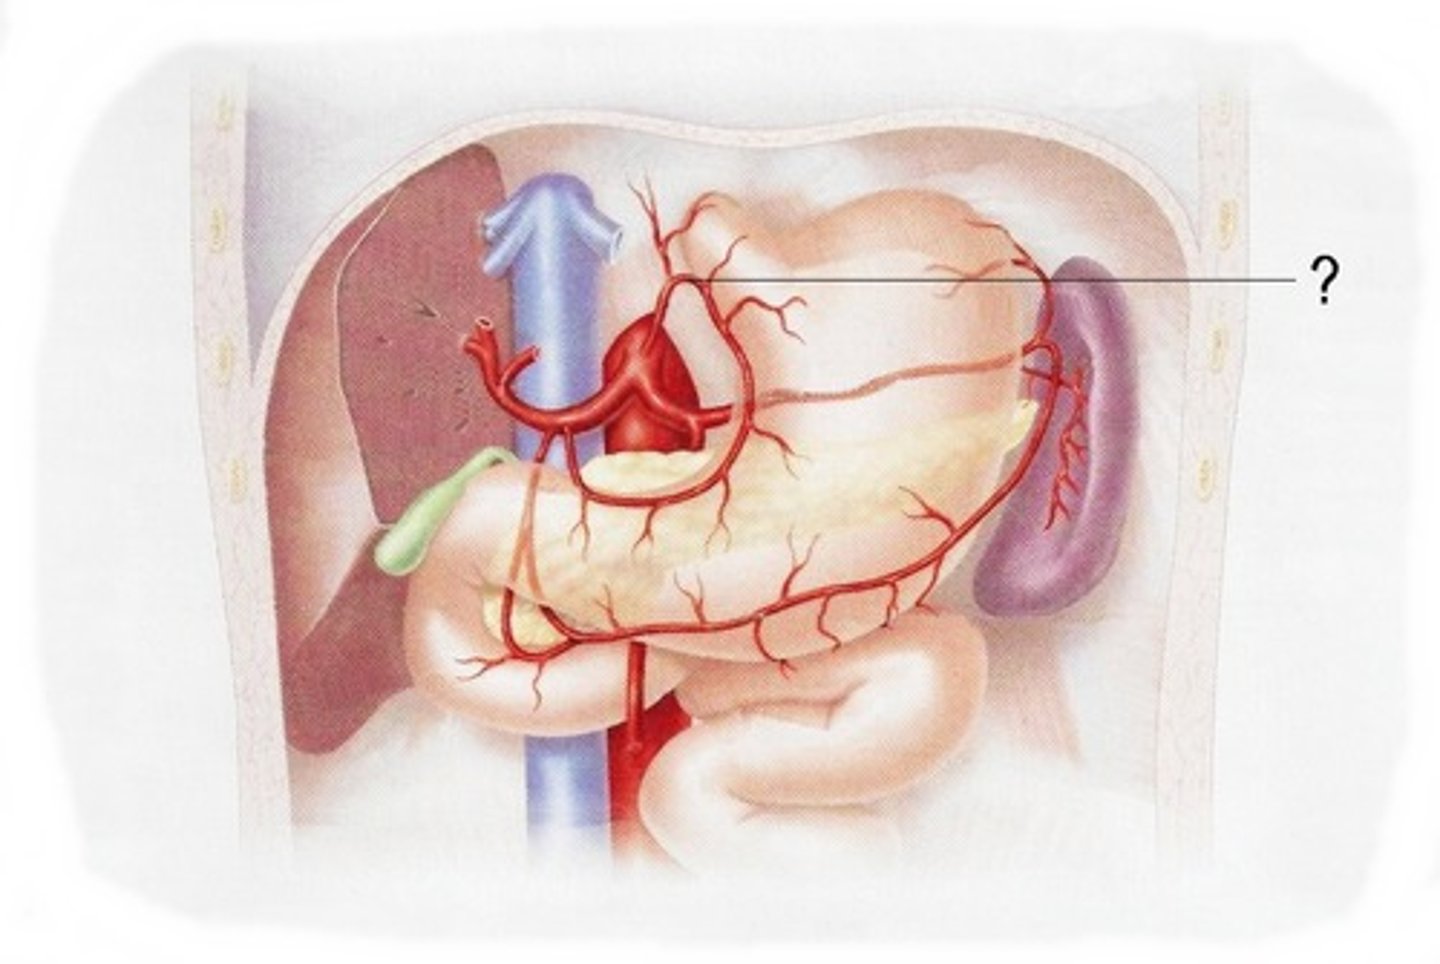

tail (of pancreas)

splenic artery